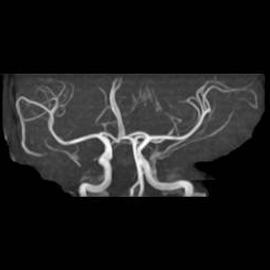

頭部MRA:脳動脈瘤の有無、血管の太さなど、脳の血管の状態を確認します

通常の頭部MRI検査では、一度にMRIとMRAの検査を行っています